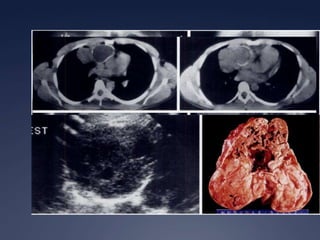

Tumor más común del timo y del mediastino anterior

15% de los tumores del mediastino

Edad: 40 a 60 años

40% Sindrome Paratímico: Miastenia Gravis, aplasia de células rojas, hipergammaglobulinemia

Encapsulado - InvasivoTimoma30%Brant and Helms:  389-416

Timoma

TimomaMasa redondaUnilateralContornos lisos o lobuladosCalcificaciones delgadas, lineales en la periferia.Engrosamiento pleural (unilat, masas o  nodular).

TimomaEncapsulada:46-75 U.H.Homogénea u ovalBien delimitada Usualmente asimétricaCalcificaciones focales 25%

Invasivo: 33-50%IrregularOblitera los planos grasos adyacentes (esternón, vasos, pleura, retroperitoneo, abdomen)Timoma invasor

Timoma invasorContraste:Reforzamiento leveHomogéneo Áreas quísticas Áreas de menor densidad

TimomaT1 isointenso al músculo T2 intensidad cercana a la de la grasaSeñal heterogénea sugiere invasión